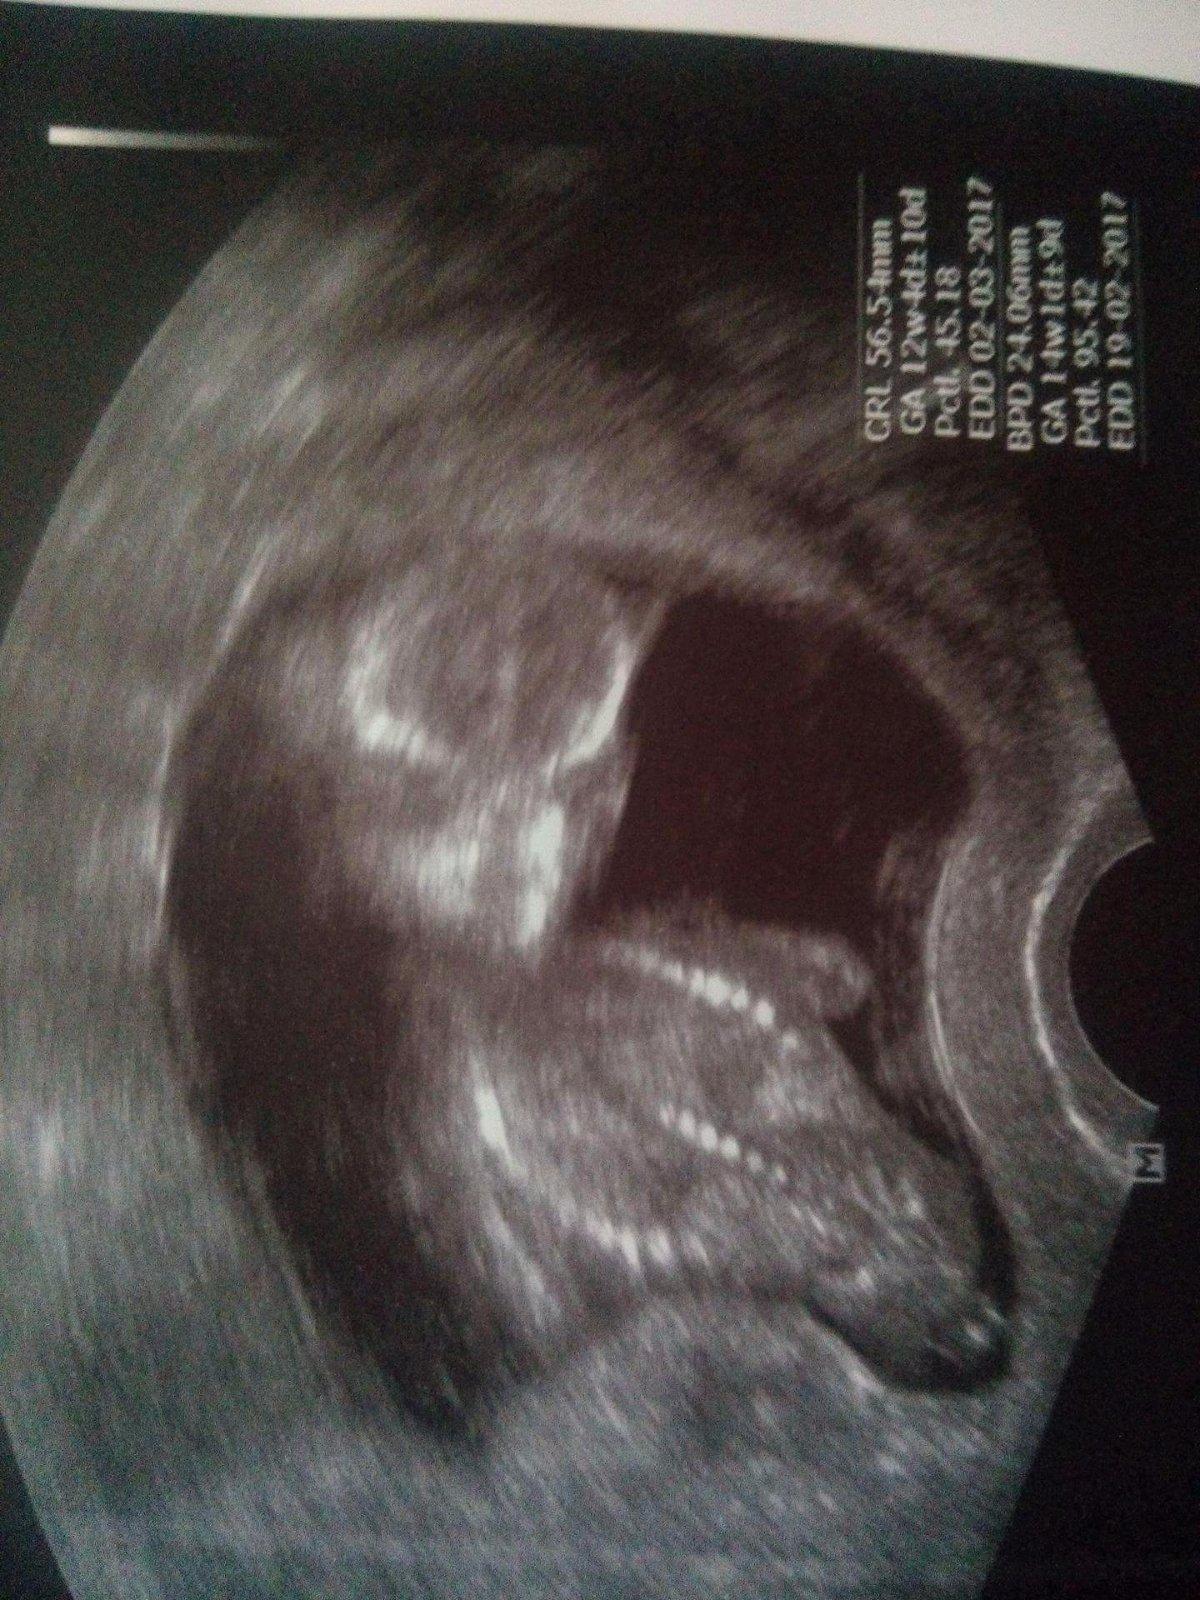

poradte, myslite ze by to mohly byt varlata ?? 🙂 😀

Myslím ty dvě malé kuličky dole 😀 jsou i na druhé fotečce

divam se, ze jste teprve ve 13. tydnu, tak beru zpet, to muze byt i paticka nohy...

zdá se mi, že je to noha, má je u sebe a nejde tam nic vidět. Ale odborník taky nejsem 😉 Myslím, že z této fotky je brzo dělat závěry

Takhle vypadá spíš holčička...ale na závěry je brzo...co doktor?😉

doktor řekl 95% kluk..ale podle čeho to usoudil to právě nevím :-/ ale mate pravdu ze by to mohla byt patička